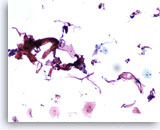

Lubricant A treated vial

…shows the effect of excessive lubricant. Superficial and Intermediate cells are clumped into a three dimensional group. Cells are less evenly dispersed with scant amorphous material noted in the background suggestive of lubricant.

10x

Lubricant A treated vial

…shows the effect of excessive lubricant. Superficial and Intermediate cells are clumped into a three dimensional group. Cells are less evenly dispersed with scant amorphous material noted in the background suggestive of lubricant.

10x